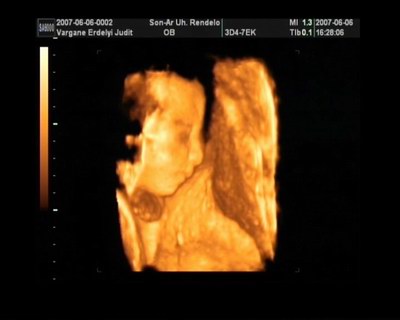

Melcsi! Nagyon határozott arcocskája van a fiadnak, karakteres, gyönyörű kispasas!